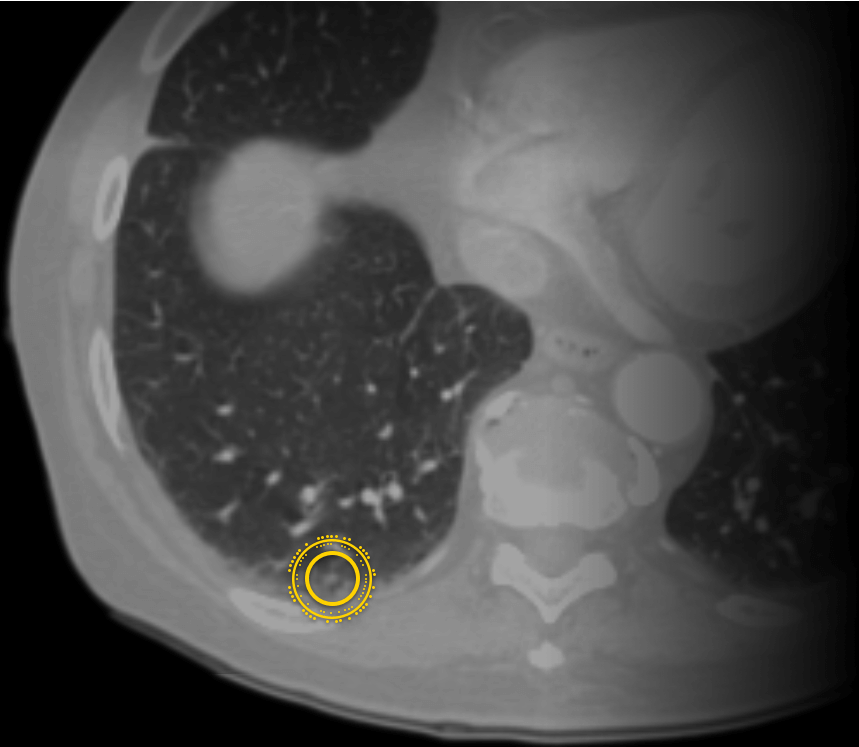

Zebra公司為患者提供基于機(jī)器學(xué)習(xí)平臺(tái)的SaaS醫(yī)學(xué)影像診斷分析服務(wù)Profound,讓患者能夠在家中快速獲取準(zhǔn)確的醫(yī)學(xué)影像分析報(bào)告。這款名為“Profound”的醫(yī)學(xué)影像分析軟件會(huì)依據(jù)掃描件中關(guān)鍵的臨床特征自動(dòng)分析,準(zhǔn)確率高達(dá)90%。

Zebra公司的醫(yī)學(xué)影像分析可以幫助醫(yī)務(wù)工作者識(shí)別出處于疾病風(fēng)險(xiǎn)期的患者,并且該網(wǎng)站會(huì)提供改善性的、預(yù)防性的治療方法,用來(lái)改善患者身體狀態(tài)。機(jī)器學(xué)習(xí)和深度學(xué)習(xí)的基礎(chǔ)是大量的高質(zhì)量數(shù)據(jù),Zebra數(shù)據(jù)庫(kù)已經(jīng)成為全球最大的醫(yī)療影像數(shù)據(jù)庫(kù)之一、全球最大的臨床醫(yī)學(xué)數(shù)據(jù)庫(kù)之一。